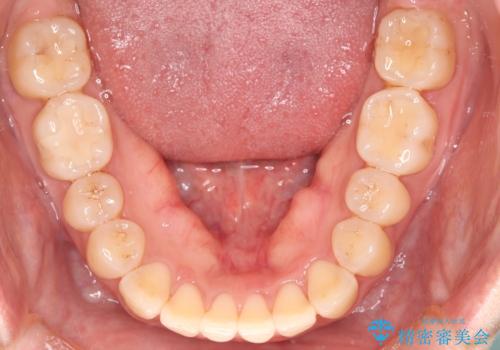

- 上の前歯の捻れを主訴に来院されました。

前歯の捻れとがたつきを改善するために、IPR(歯と歯の間を削る処置)と歯列拡大をすることで歯並びを整えていく治療計画を立てました。